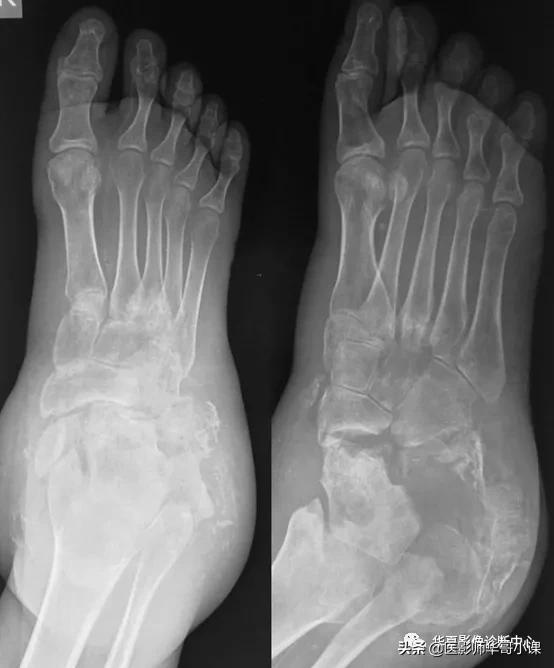

- 手和足

- 病因:麻风病(外伤和继发细菌感染所致)

- 鹰爪手、鹰爪趾

- “棒棒糖杆”样跖(指)骨表现/逐渐变细的指骨(骨向中心萎缩所致骨变短、变窄)

- 鉴别诊断:冻疮、恶性贫血、硬皮病、脊髓空洞症、运动性共济失调、家族性感觉神经病

- 足和踝

- 病因:长期难以控制的糖尿病、梅毒

- 软组织肿胀、发热、红斑

- 部位:通常由中足开始

- 血管钙化

- 半脱位(起始于第2跖跗关节)

- 跟骨后结节撕脱性骨折

- 第2趾骨头软骨下骨折

- 距(骨)舟(骨)的移位伴中足骨病变

- 鉴别诊断:骨髓炎、脓毒性关节炎(通常局限于一个关节)

左足跖跗关节神经性骨关节病,第2~5跖跗关节及跗舟关节骨质破坏,破坏区周围可见碎骨片,跖骨间可见血管钙化。左足第1~2跖骨基底部及对应跗骨间可见Lisfranc脱位。

跟骨破坏,距骨舟骨关节脱位,近端跗骨吸收,跗关节紊乱,软组织肿胀,动脉钙化。